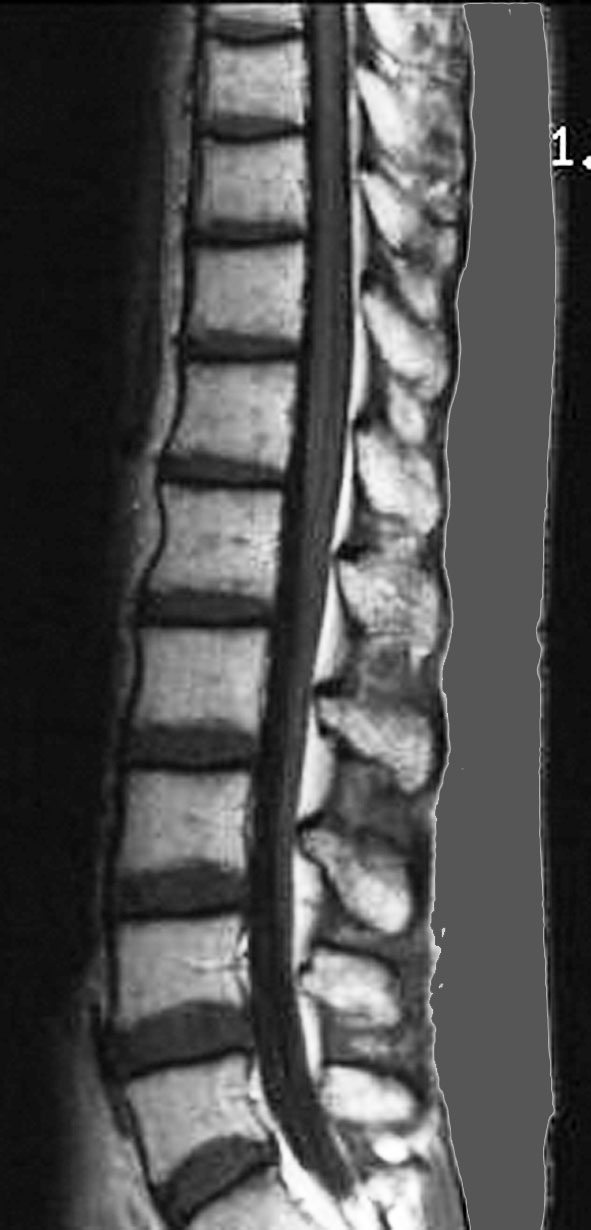

脊髄にも再発は見られませんでした。